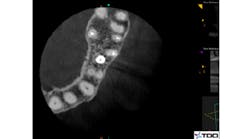

It is crucial to understand that a true endodontic failure can always be attributed to the presence of bacteria in the canal system or in the peririadicular tissues. The practitioner should determine the likely source of bacteria. Bacterial removal and elimination of infection are the ultimate goals of a successful retreatment. (2) This is done through proper diagnostic testing, radiographic assessment, and clinical judgment. Figure 1 shows an axial CBCT image of an untreated MB2 canal in the maxillary first molar.